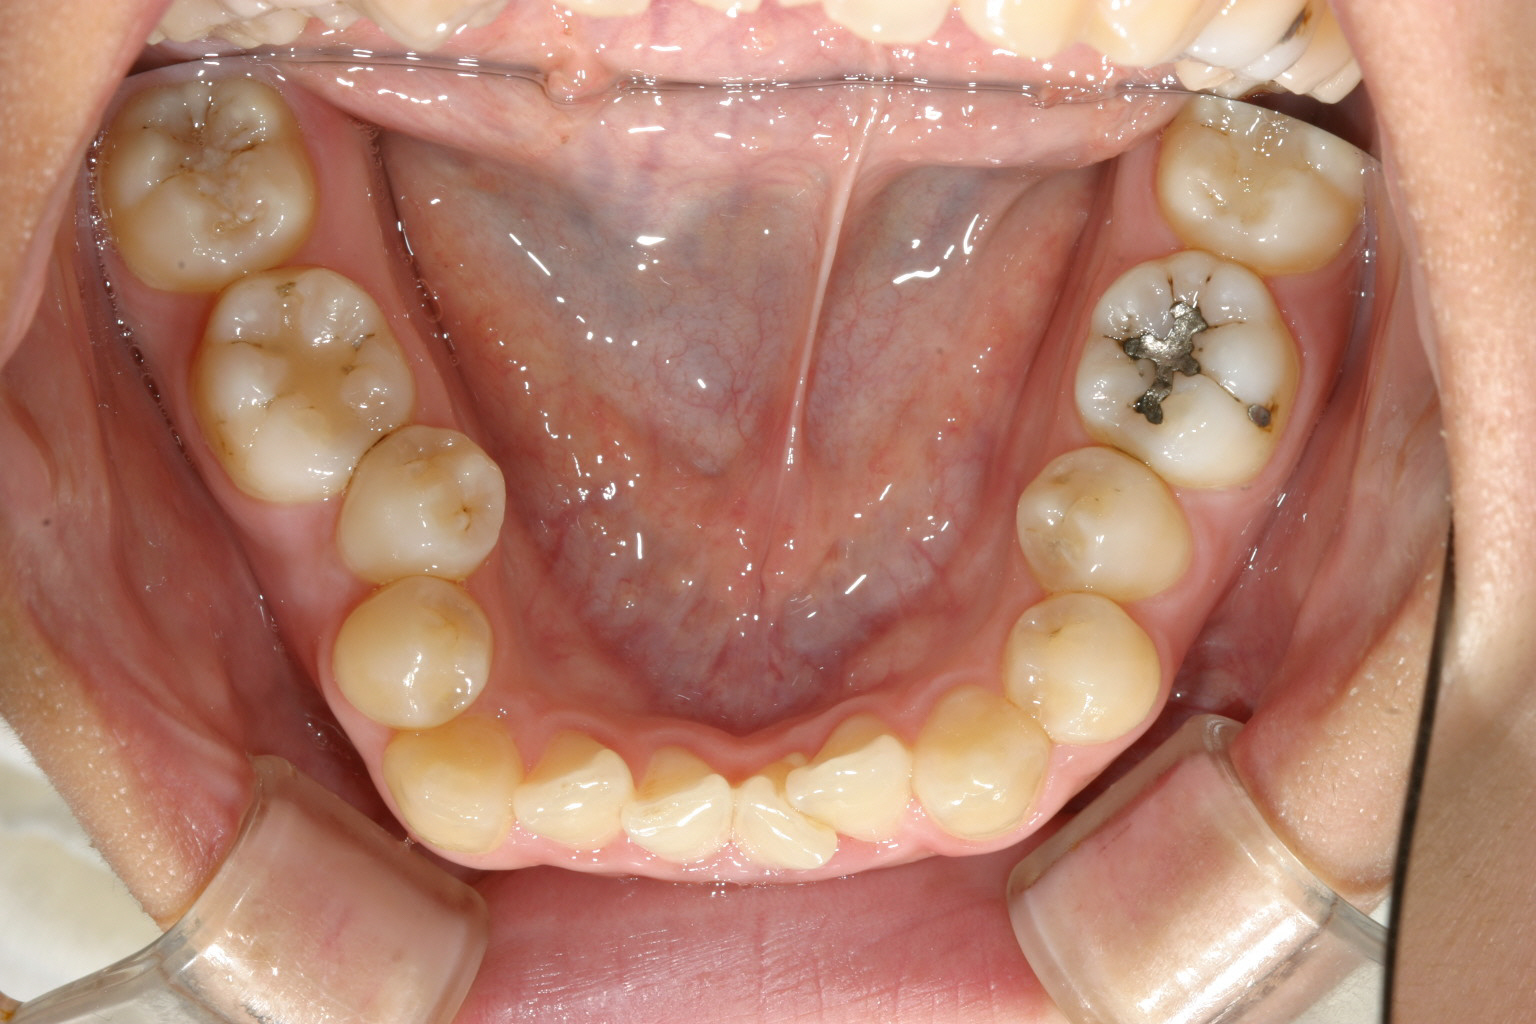

前歯に結構な叢生が見受けられます。

下顎にも上顎同様アーチがつぶれスクエアーになっています。